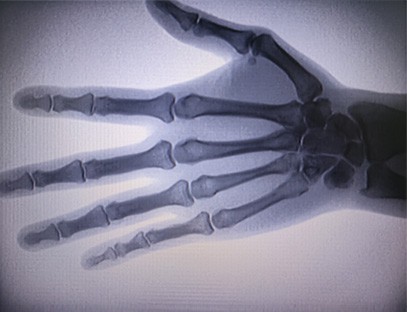

Is ionstraim iniompartha é meaisín X-gha iniompartha As-c200 le dáileog radaíochta beag agus an-sábháilte. Tá sé oiriúnach go háirithe d'aonaid agus do dhaoine aonair nach bhfuil dóthain buiséid acu agus riachtanais íseal le haghaidh pictiúr. Tá an ghlúin nua feistithe le scáileán mór 10 orlach ard-sainmhínithe, a bhfuil raon peirspictíochta níos mó aige agus is féidir leis an pailme iomlán a dhearcadh go hiomlán. Tá sé oiriúnach den chuid is mó le haghaidh peirspictíocht ortaipéideach leighis. Is féidir é a nascadh le printéir scannáin chun scannáin ortaipéideacha a phriontáil, agus is féidir é a úsáid freisin i dtáirgeadh agus i dtástáil tionsclaíoch. Gan seomra dorcha, peirspictíocht dhíreach, breathnóireacht ar an toirt, íomháú ardtaifeach agus soiléir.

Is táirge ardchaighdeáin é ár Meaisín X-gha Ortaipéideach a dearadh go háirithe le haghaidh íomháithe ortaipéideacha. Is féidir é a úsáid le haghaidh diagnóis agus pleanáil cóireála ar choinníollacha ortaipéideacha éagsúla, lena n-áirítear bristeacha, dislocations, airtríteas, agus siadaí cnámh. Tá sé feistithe le teicneolaíocht X-gha chun cinn a chuireann ar chumas íomhánna ardcháilíochta le nochtadh radaíochta laghdaithe. Tá córas íomháithe ardtaifigh ag an meaisín agus is féidir íomhánna d'aon struchtúr cnámh a ghabháil le soiléireacht mhór.

1. Teicneolaíocht íomháithe chun cinn: Úsáideann ár Meaisín X-gha Ortaipéideach teicneolaíocht íomháithe chun cinn chun íomhánna ardchaighdeáin de chnámha agus hailt a ghabháil, ag soláthar diagnóis chruinn agus torthaí cóireála feabhsaithe.